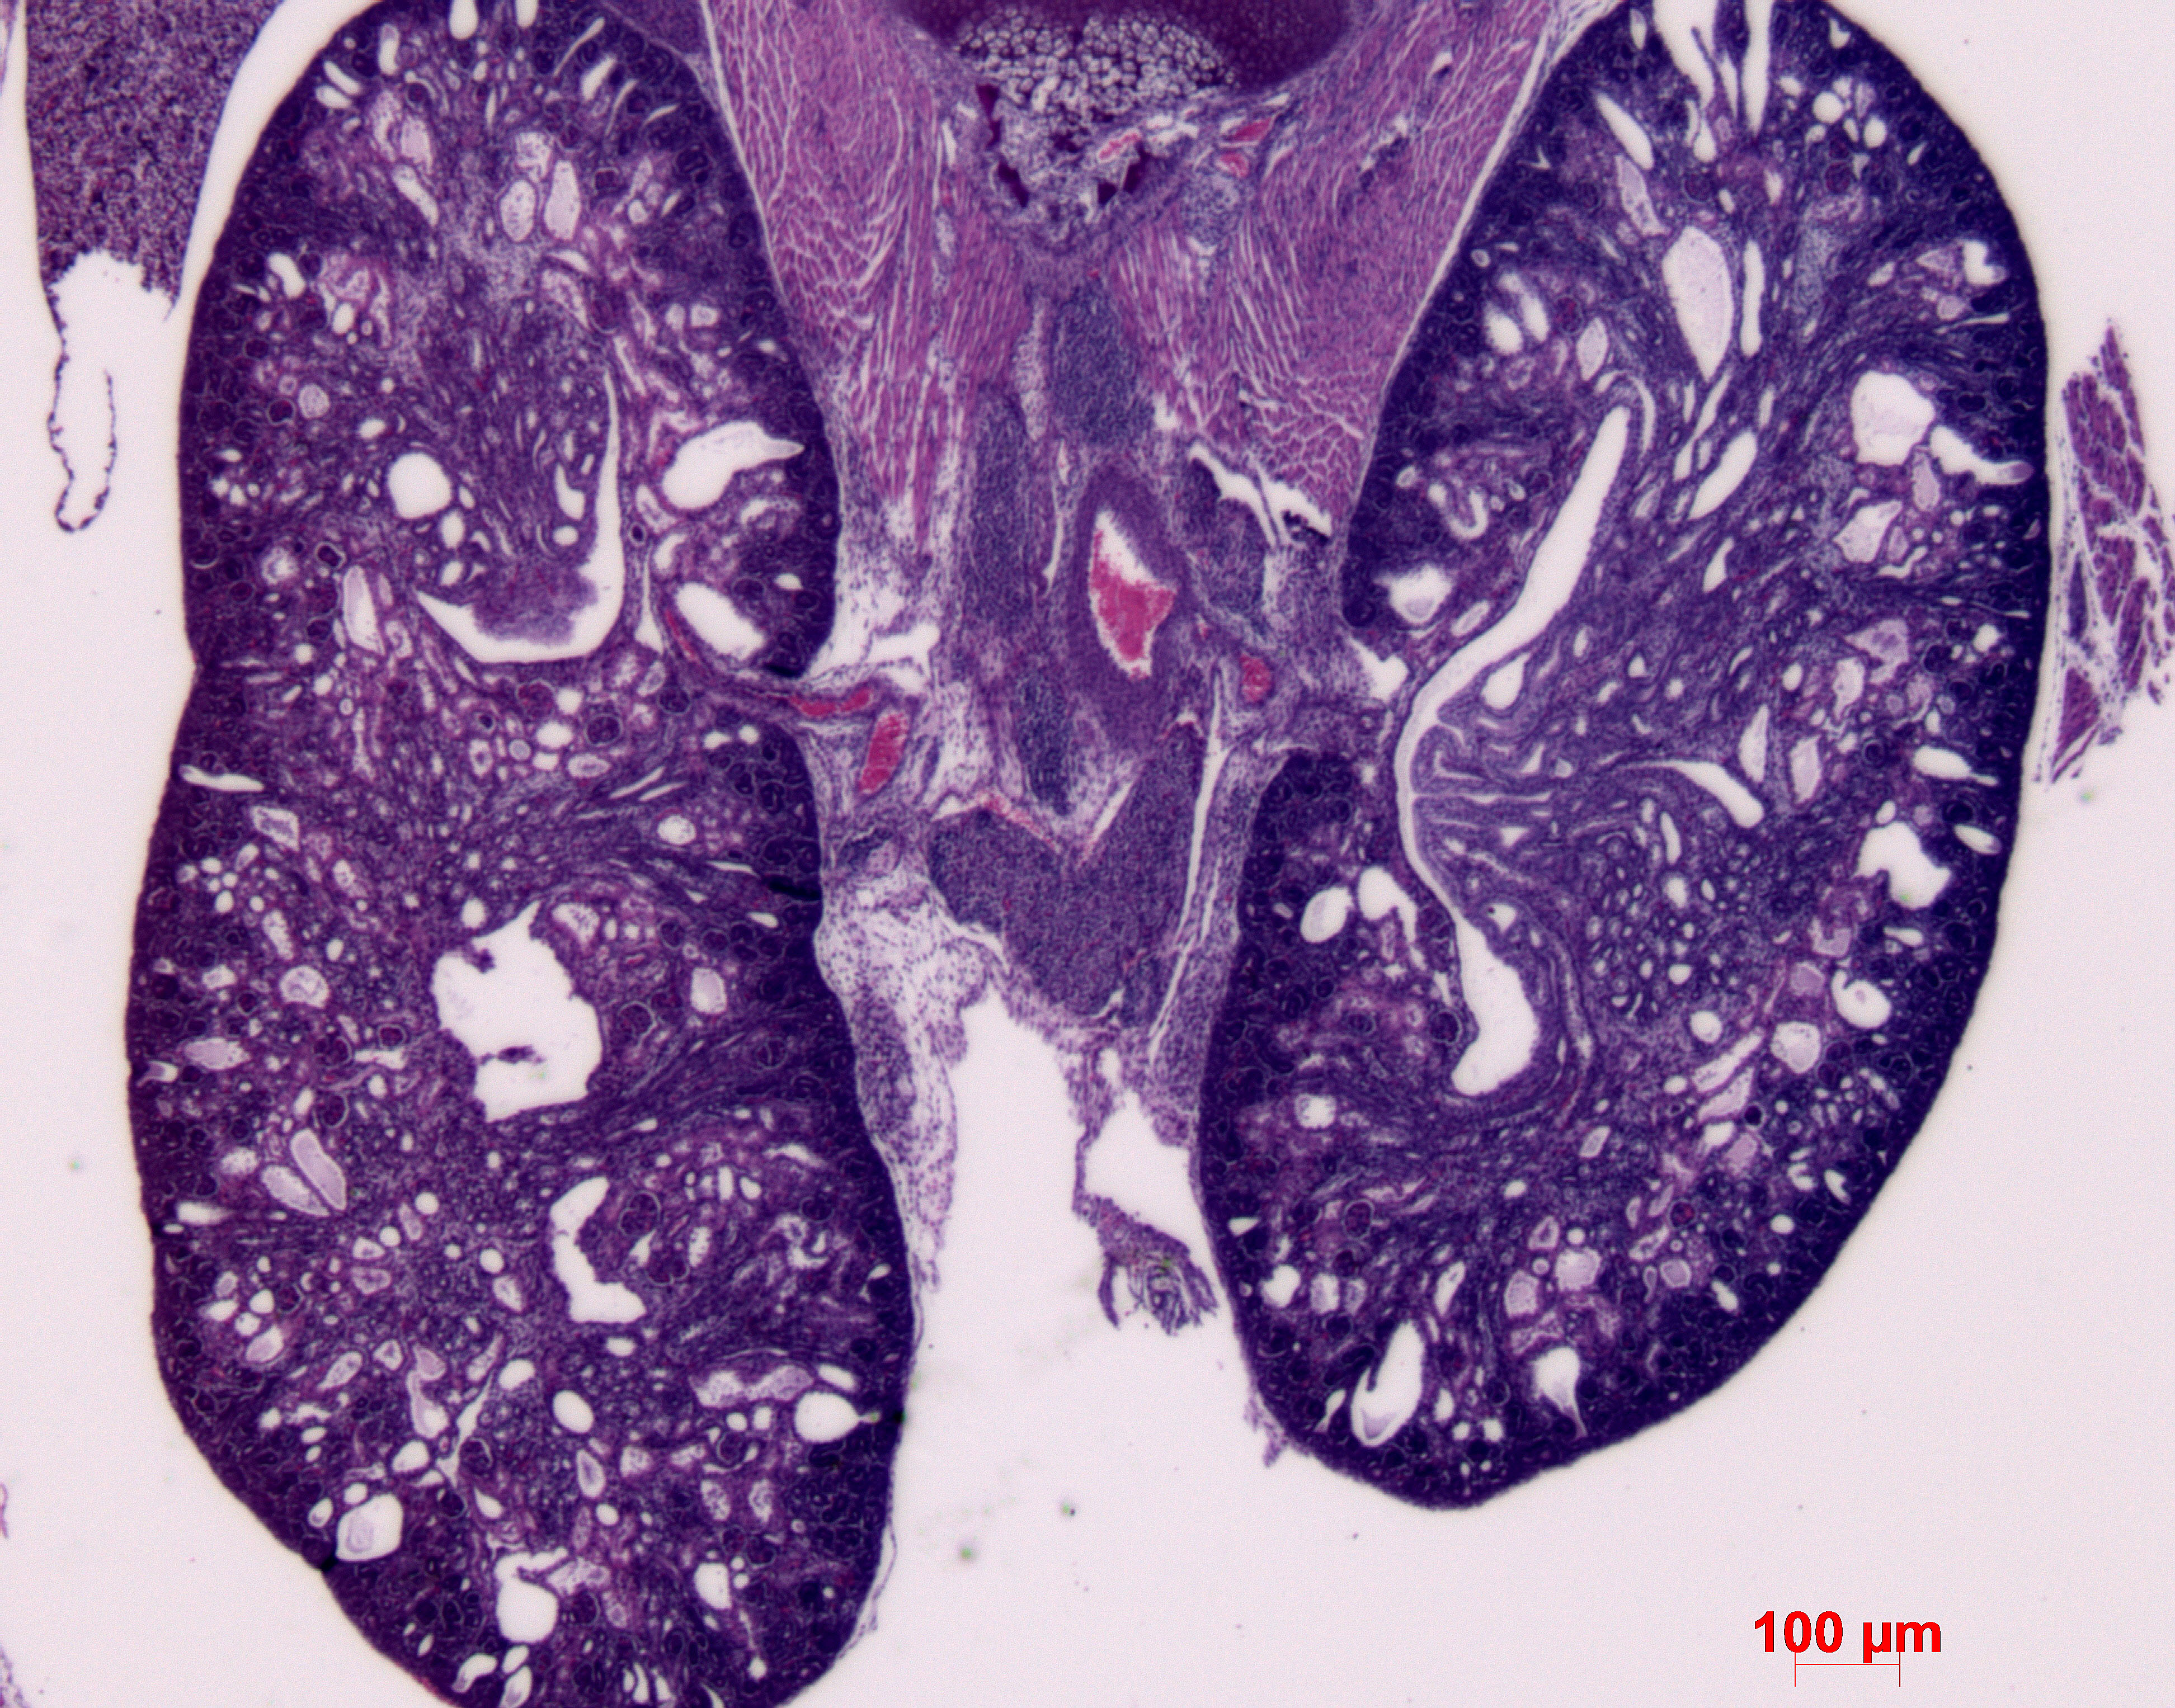

Caption Mutant 1291-006-LA shows bilateral cystic kidneys

b2b1291Clo Mutant line 1291; Bench to Bassinet Program (B2B/CVDC), mutation 1291 Cecilia Lo

Tmem67b2b1291.1Clo transmembrane protein 67; Bench to Bassinet Program (B2B/CVDC), mutation 1291, subline 1 Cecilia Lo

b2b1291Clo/b2b1291Clo C57BL/6J-b2b1291Clo

Tmem67b2b1291.1Clo/Tmem67b2b1291.1Clo C57BL/6J-Tmem67b2b1291.1Clo